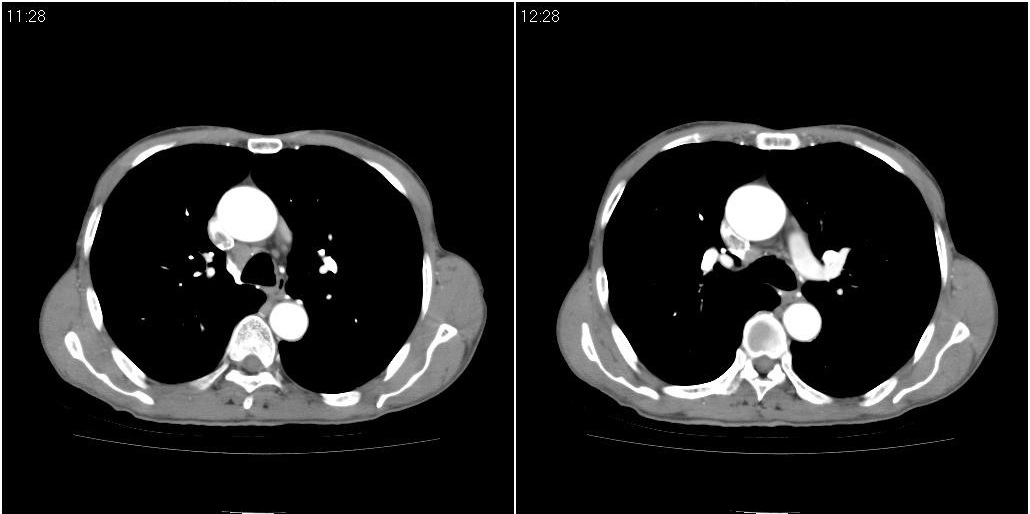

1)右肺中叶慢性炎症并支气管扩张,节段性肺不张。2)两肺下叶支气管扩张。